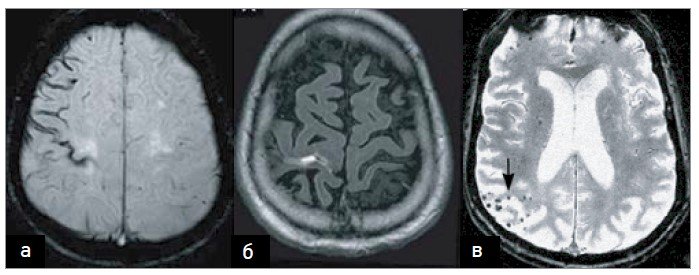

Магнітний резонанс? Геніально. Це допомагає виявити найменші зміни в мозку. Медицині важливо не здаватися на півдорозі.